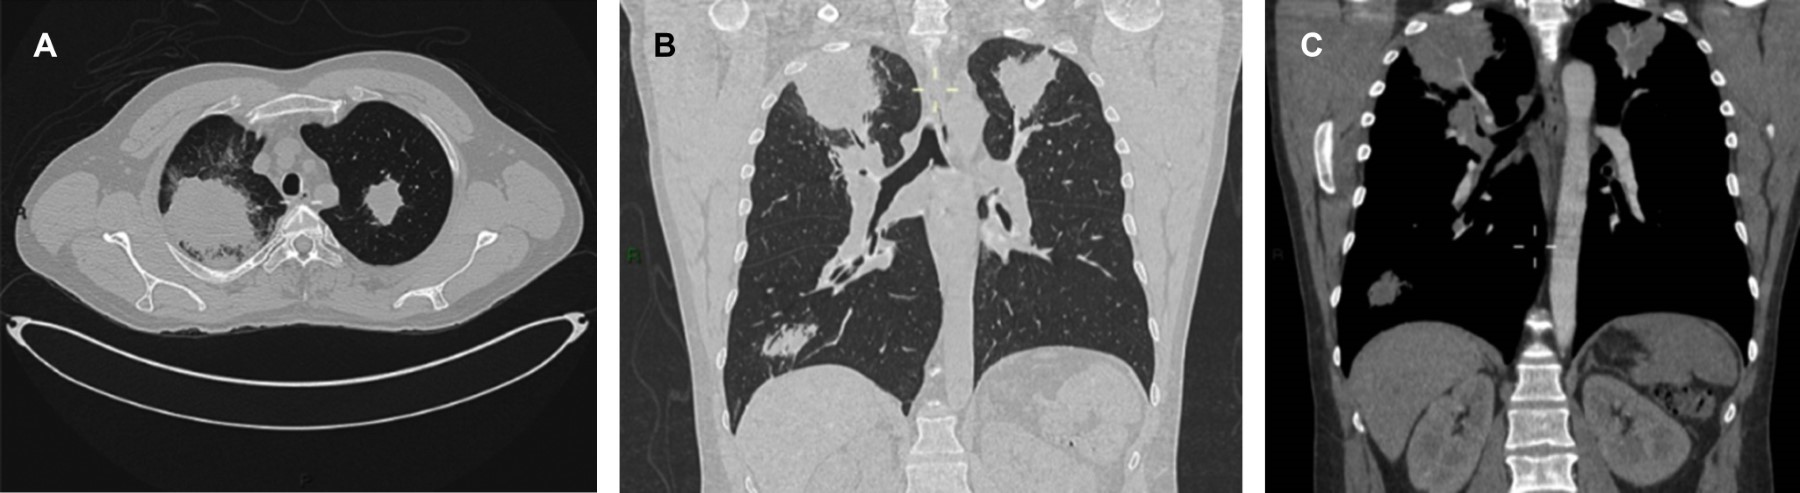

Granulomatosis with polyangiitis

Granulomatosis with polyangiitis is the most common vasculitis associated with anti-neutrophil cytoplasmic antibodies, although it has a low incidence and prevalence. The diagnosis is confirmed by serology and histopathology of the affected organ or system; its manifestations may be heterogeneous when possible. Without the correct treatment, your estimated survival is five months after diagnosis. Below, we report the case of a 50-year-old man who was hospitalized due to weight loss, chronic sinusitis, and lung injuries.

Figure 1

Figure 2

Figure 3